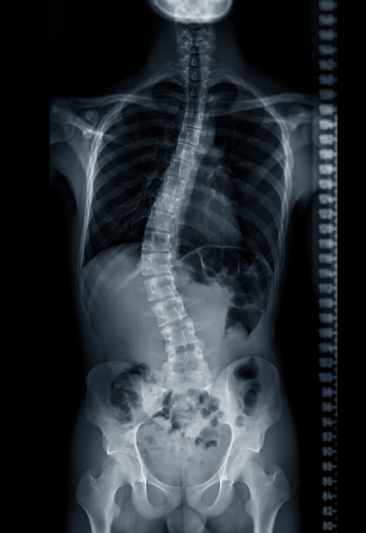

Living with scoliosis can bring challenges such as back pain, uneven posture, and limited mobility. But beyond the physical, scoliosis often affects how people feel about themselves. Changes in body shape, posture, or wearing a brace during formative years can deeply impact self-esteem and emotional health.

Yoga therapy offers a holistic, compassionate way to manage scoliosis, addressing both the body and the mind. Through mindful movement and exercises tailored to your unique curve, soft tissue release, breathwork, and self-awareness practices, you’ll not only find physical relief but also build confidence, resilience, and a deeper acceptance of your body.

Personalized practices tailored to different scoliosis patterns (C-curve, S-curve, thoracic, lumbar).